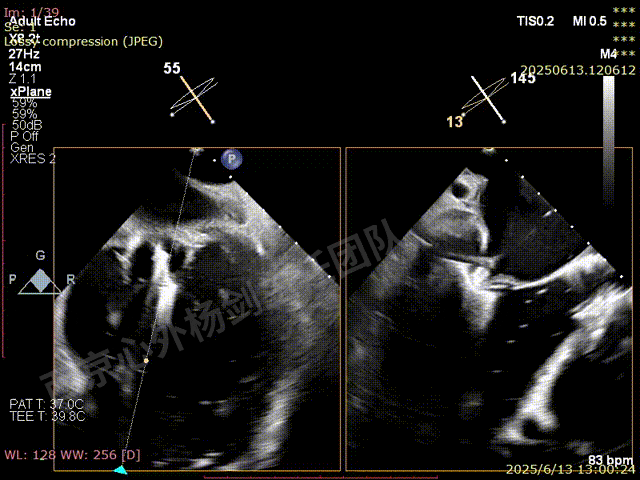

术前超声检查

图片

TAVR术后,全心增大,二尖瓣反流重度,三尖瓣反流重度。中量心包积液。左室严重增大,标准图像调整困难。主动脉瓣位带支架人工瓣膜瓣叶启闭正常,主动脉瓣位人工瓣上血流速度Vmax 148cm/s,PGmax 9mmHg,Vmean 86cm/s,PGmean 2mmHg, VTI 34.7cm,瓣周反流(轻)。估测肺动脉收缩压约49mmHg;左室收缩功能明显减低。LVEF:23%,EDV:364ml,ESV:221ml。

彩色血流示:二尖瓣反流缩流颈彩宽6.6mm,面积17cm²,容积30ml;二尖瓣瓣口面积6.6cm²,瓣环内径:左右径34mm,前后径34mm。2区瓣叶长度:前叶36mm,后叶20mm,叶环比1.6. 三尖反流面积17.2cm²,容积33ml,Vmax 291cm/s,PGmax 34mmHg。